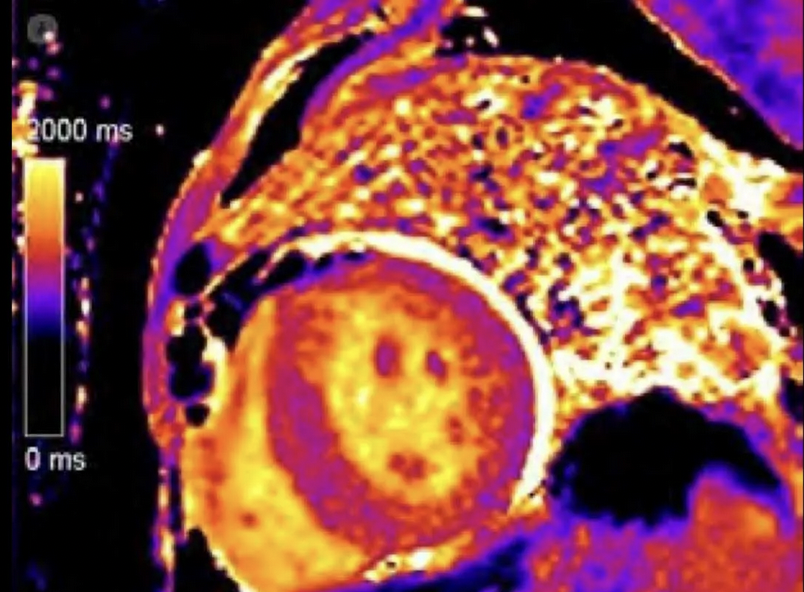

Importancia pronóstica del acoplamiento ventriculoarterial derecho en pacientes sometidos a cirugía aislada de la válvula tricúspide #REC Manuel Carnero Julian P Villacastin Alberto de Agustin Eduardo Pozo revespcardiol.org/es-importancia…

Prognostic significance of right ventriculoarterial coupling in patients undergoing isolated tricuspid valve surgery #REC Manuel Carnero Julian P Villacastin Alberto de Agustin Eduardo Pozo revespcardiol.org/en-prognostic-…